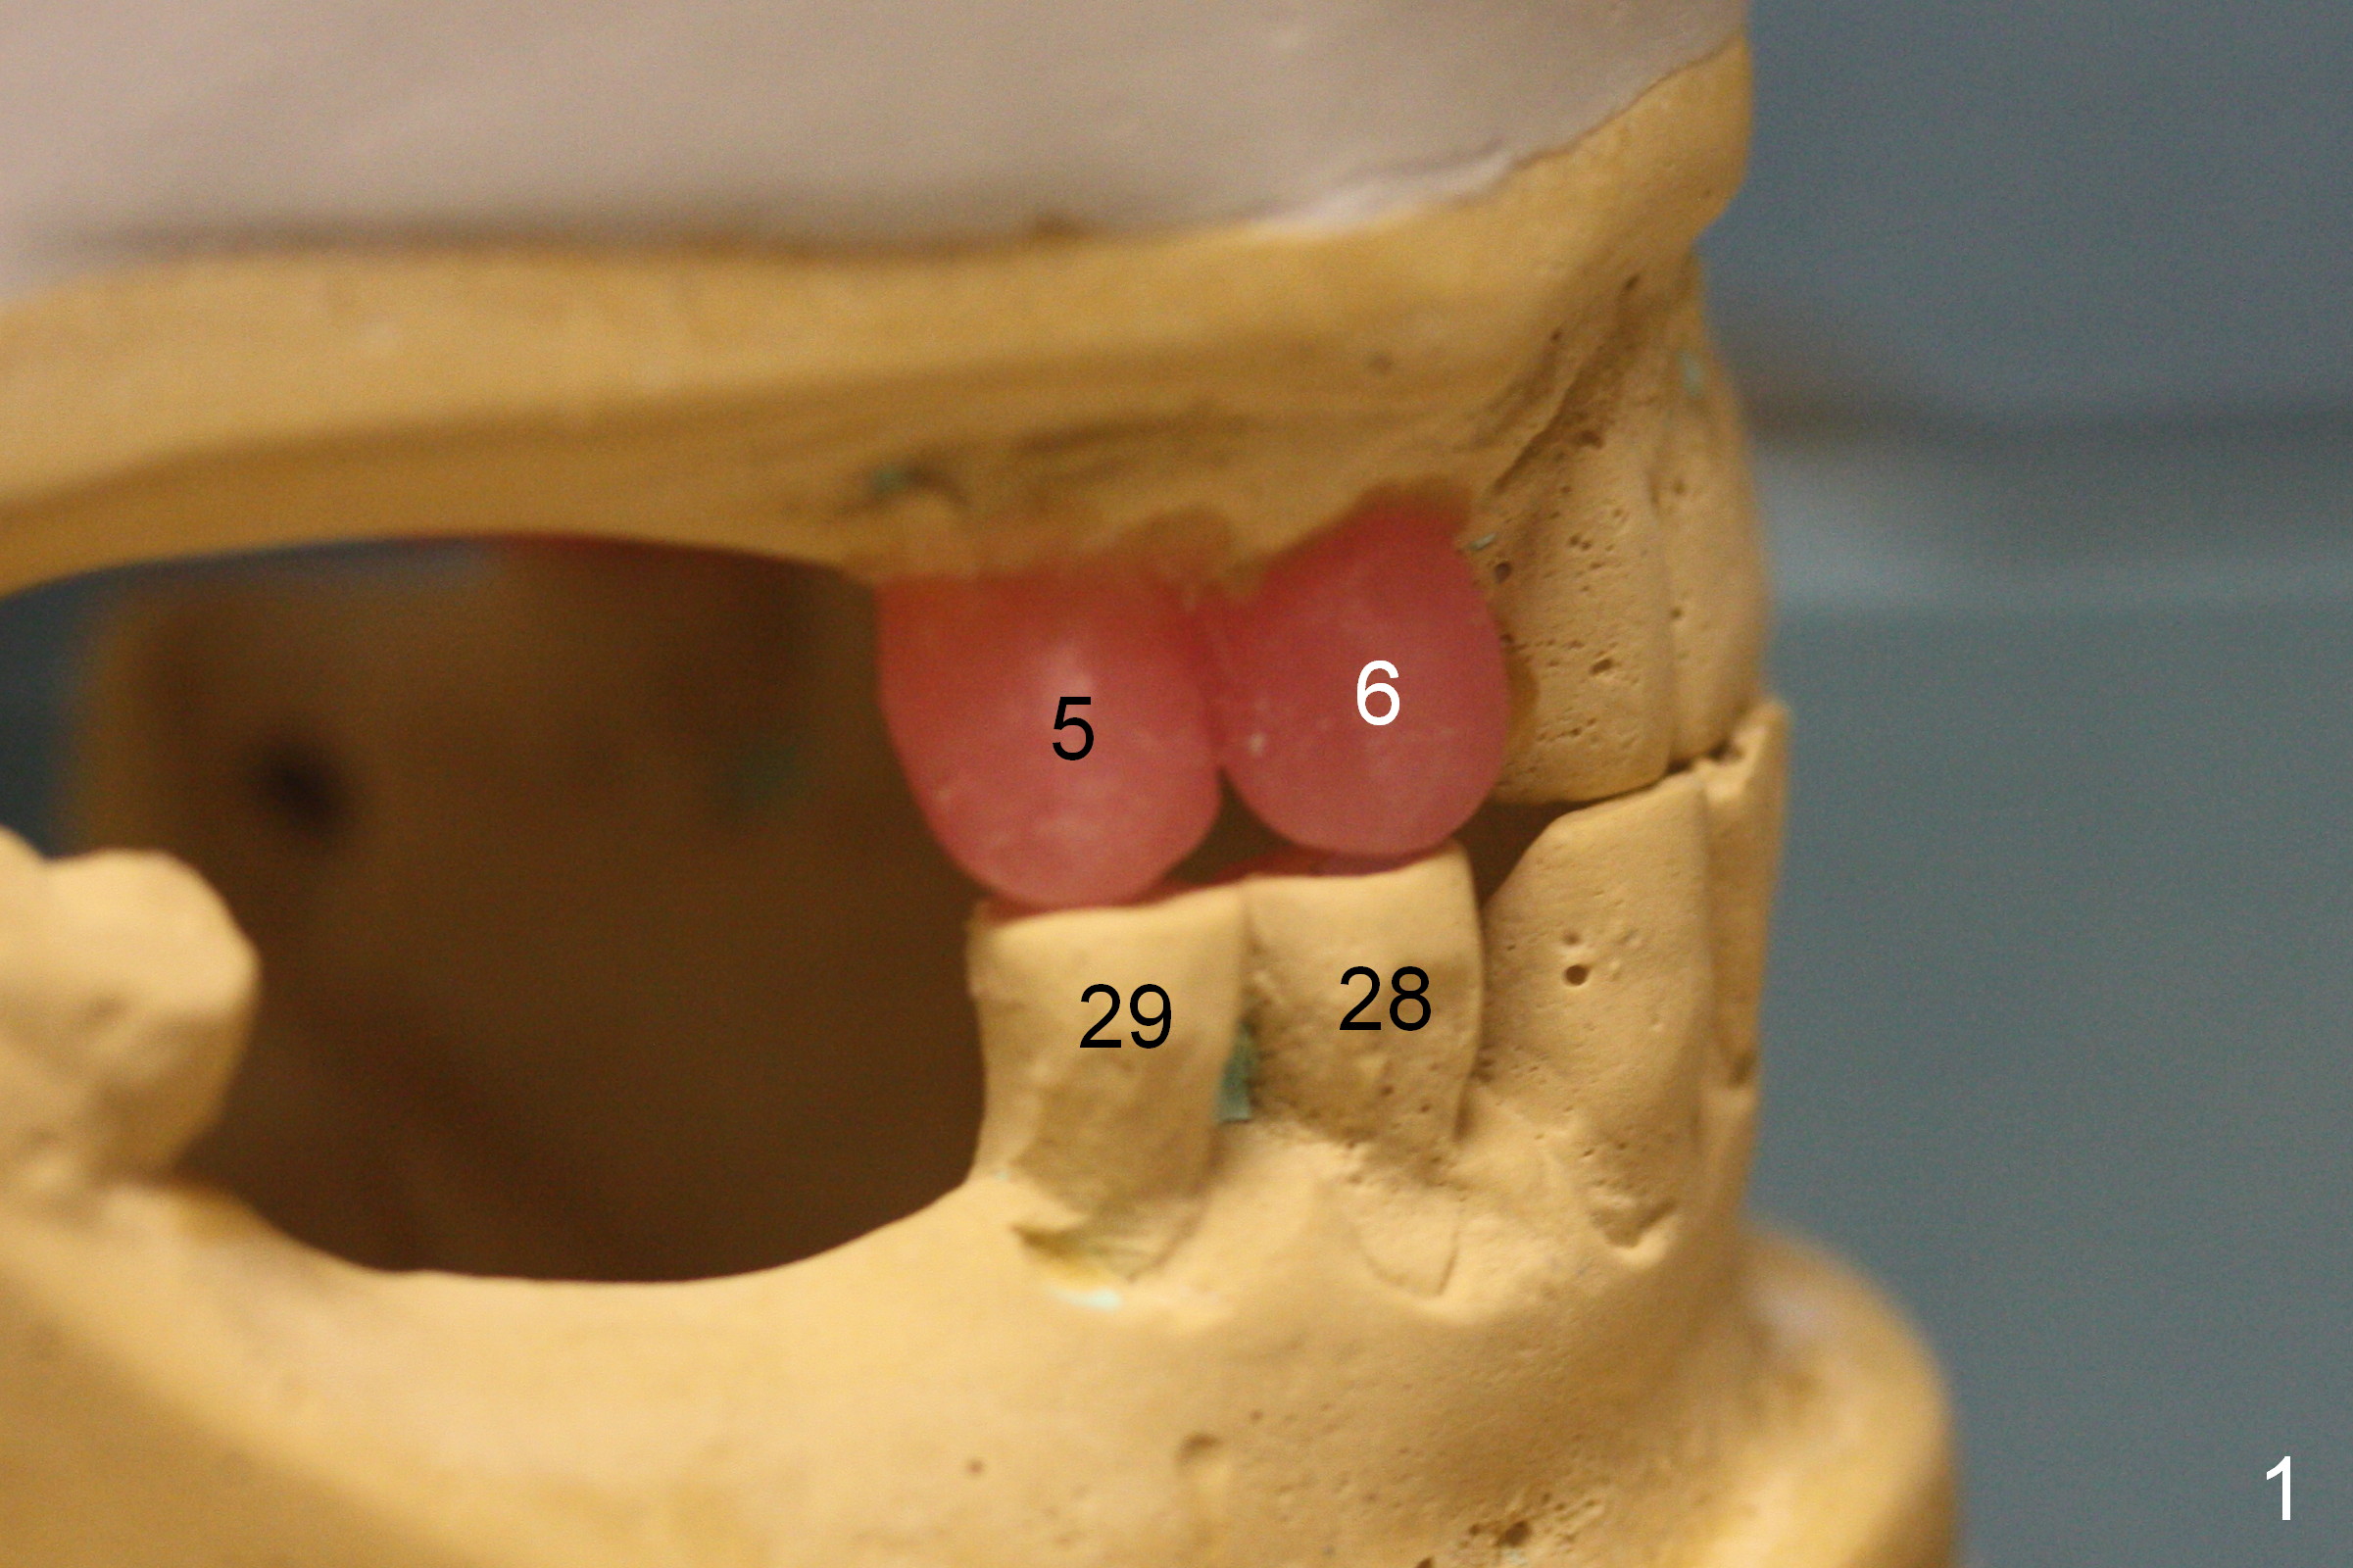

A 70-year-old man (CK) requests restoration of the upper arch with implants, because he is not used to a partial denture. Due to cross bite (Fig.1-3), one less implant can be placed in each of the posterior region (Fig.1, 3).

The patient prefers to have implant placement on the right side first. The implant at #5 should be placed a little more distal in order to have enough clearance (2-3 mm) between the implants at #5,6 (Fig.4 (thick section), 5 (thin section of CBCT)). Note the kissing periapical radiolucency at #5 and 6 (Fig.5 *). After residual root extraction, the sockets will be soaked with 2% Xylocaine/1:50,000 Epinephrine.

Fig.6,7 are coronal sections of the teeth #5 and 6, respectively. The buccal (B) plate is completely (Fig.6) or partially (Fig.7) lost. Osteotape is to be inserted between the buccal gingiva and the implant.